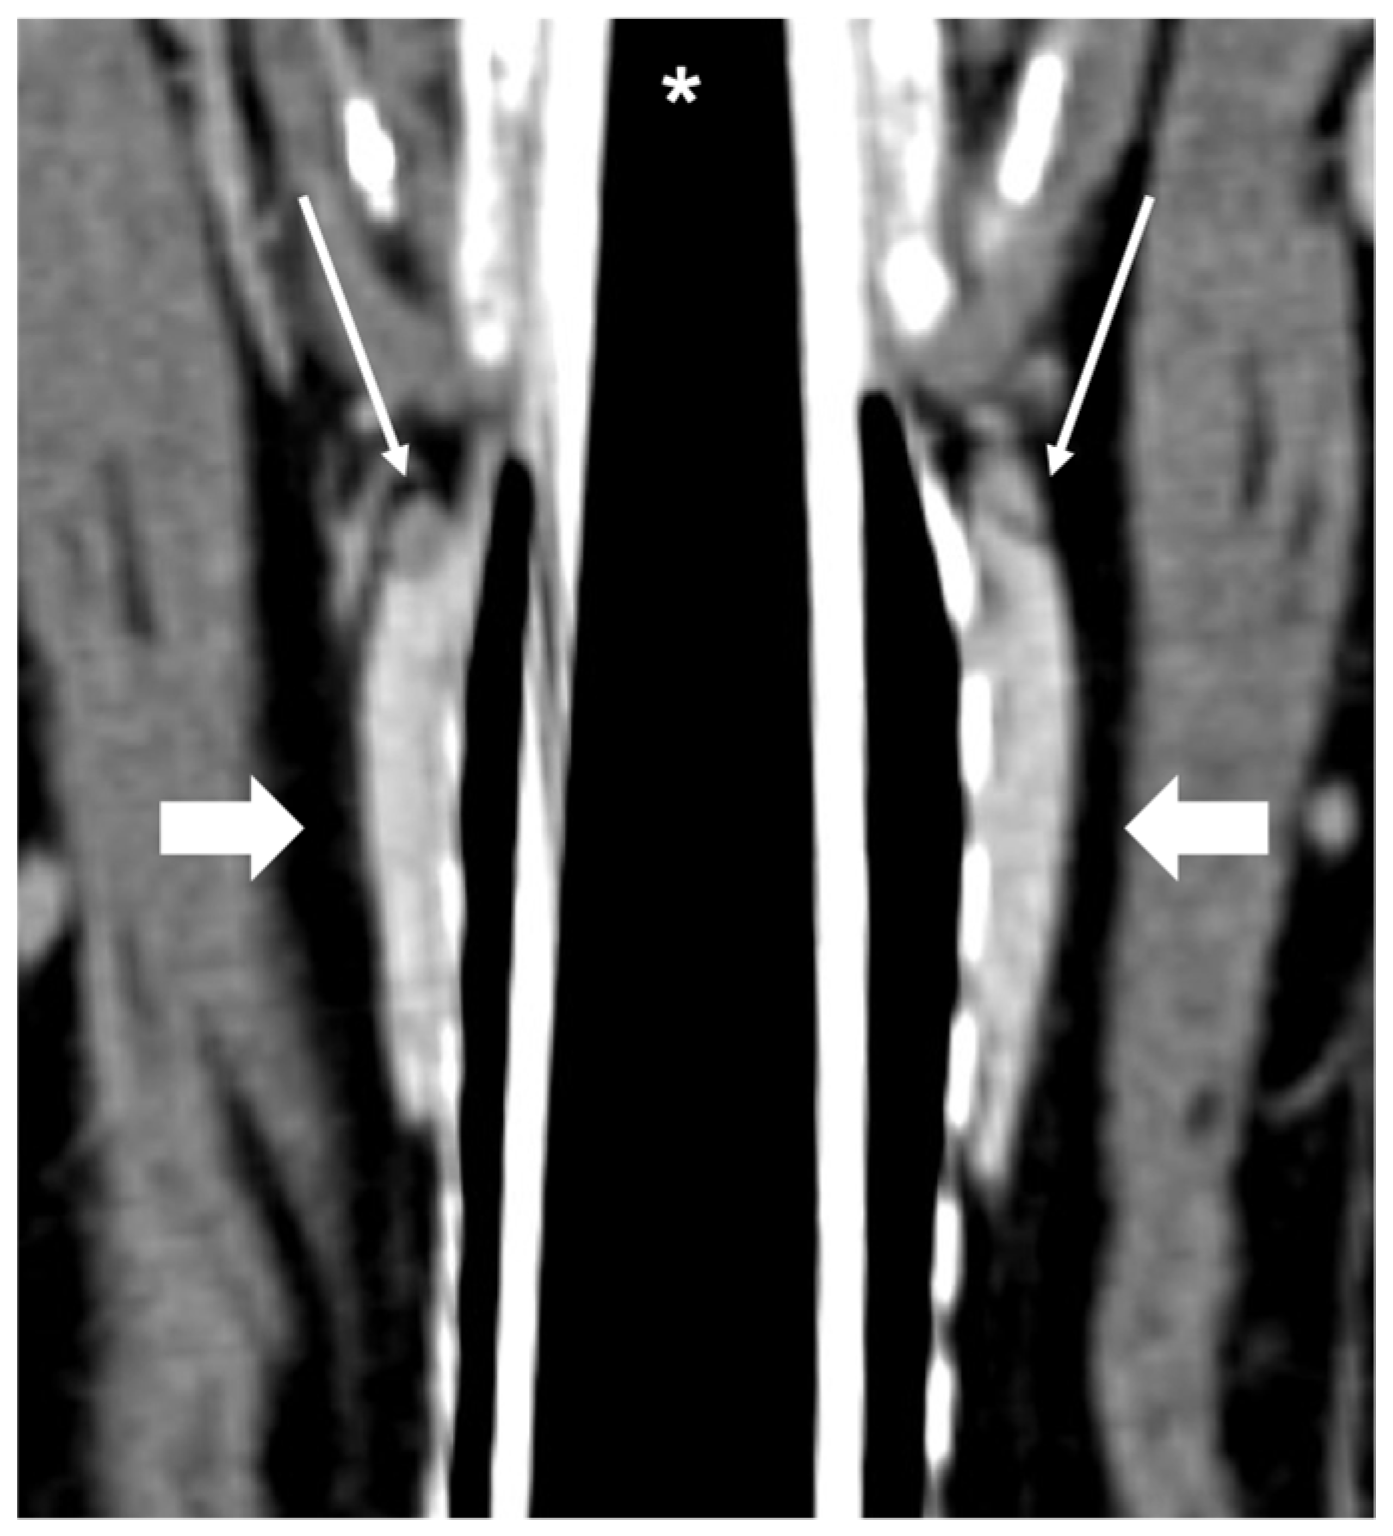

Figure 2.

CT appearance of normal external parathyroid glands. Post-contrast dorsal CT reconstruction showing external parathyroid glands (thin arrows), visible at the cranial part of both thyroid lobes (large arrows); the left and right thyroid lobes and respective external parathyroid glands are all visible in this single image. * Trachea with endotracheal tube.